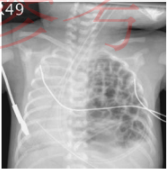

27.吳先生使用呼吸器,放置中央靜脈導管與鼻胃管,發生呼吸困難,其胸部 X 光如下, 應最優先執行下列何項處置?(A) 插上胸管(B) 更換強效抗生素使用(C) 安排胸部電腦斷層確認病因(D) 調高呼吸器給氣壓力以改善呼吸困難